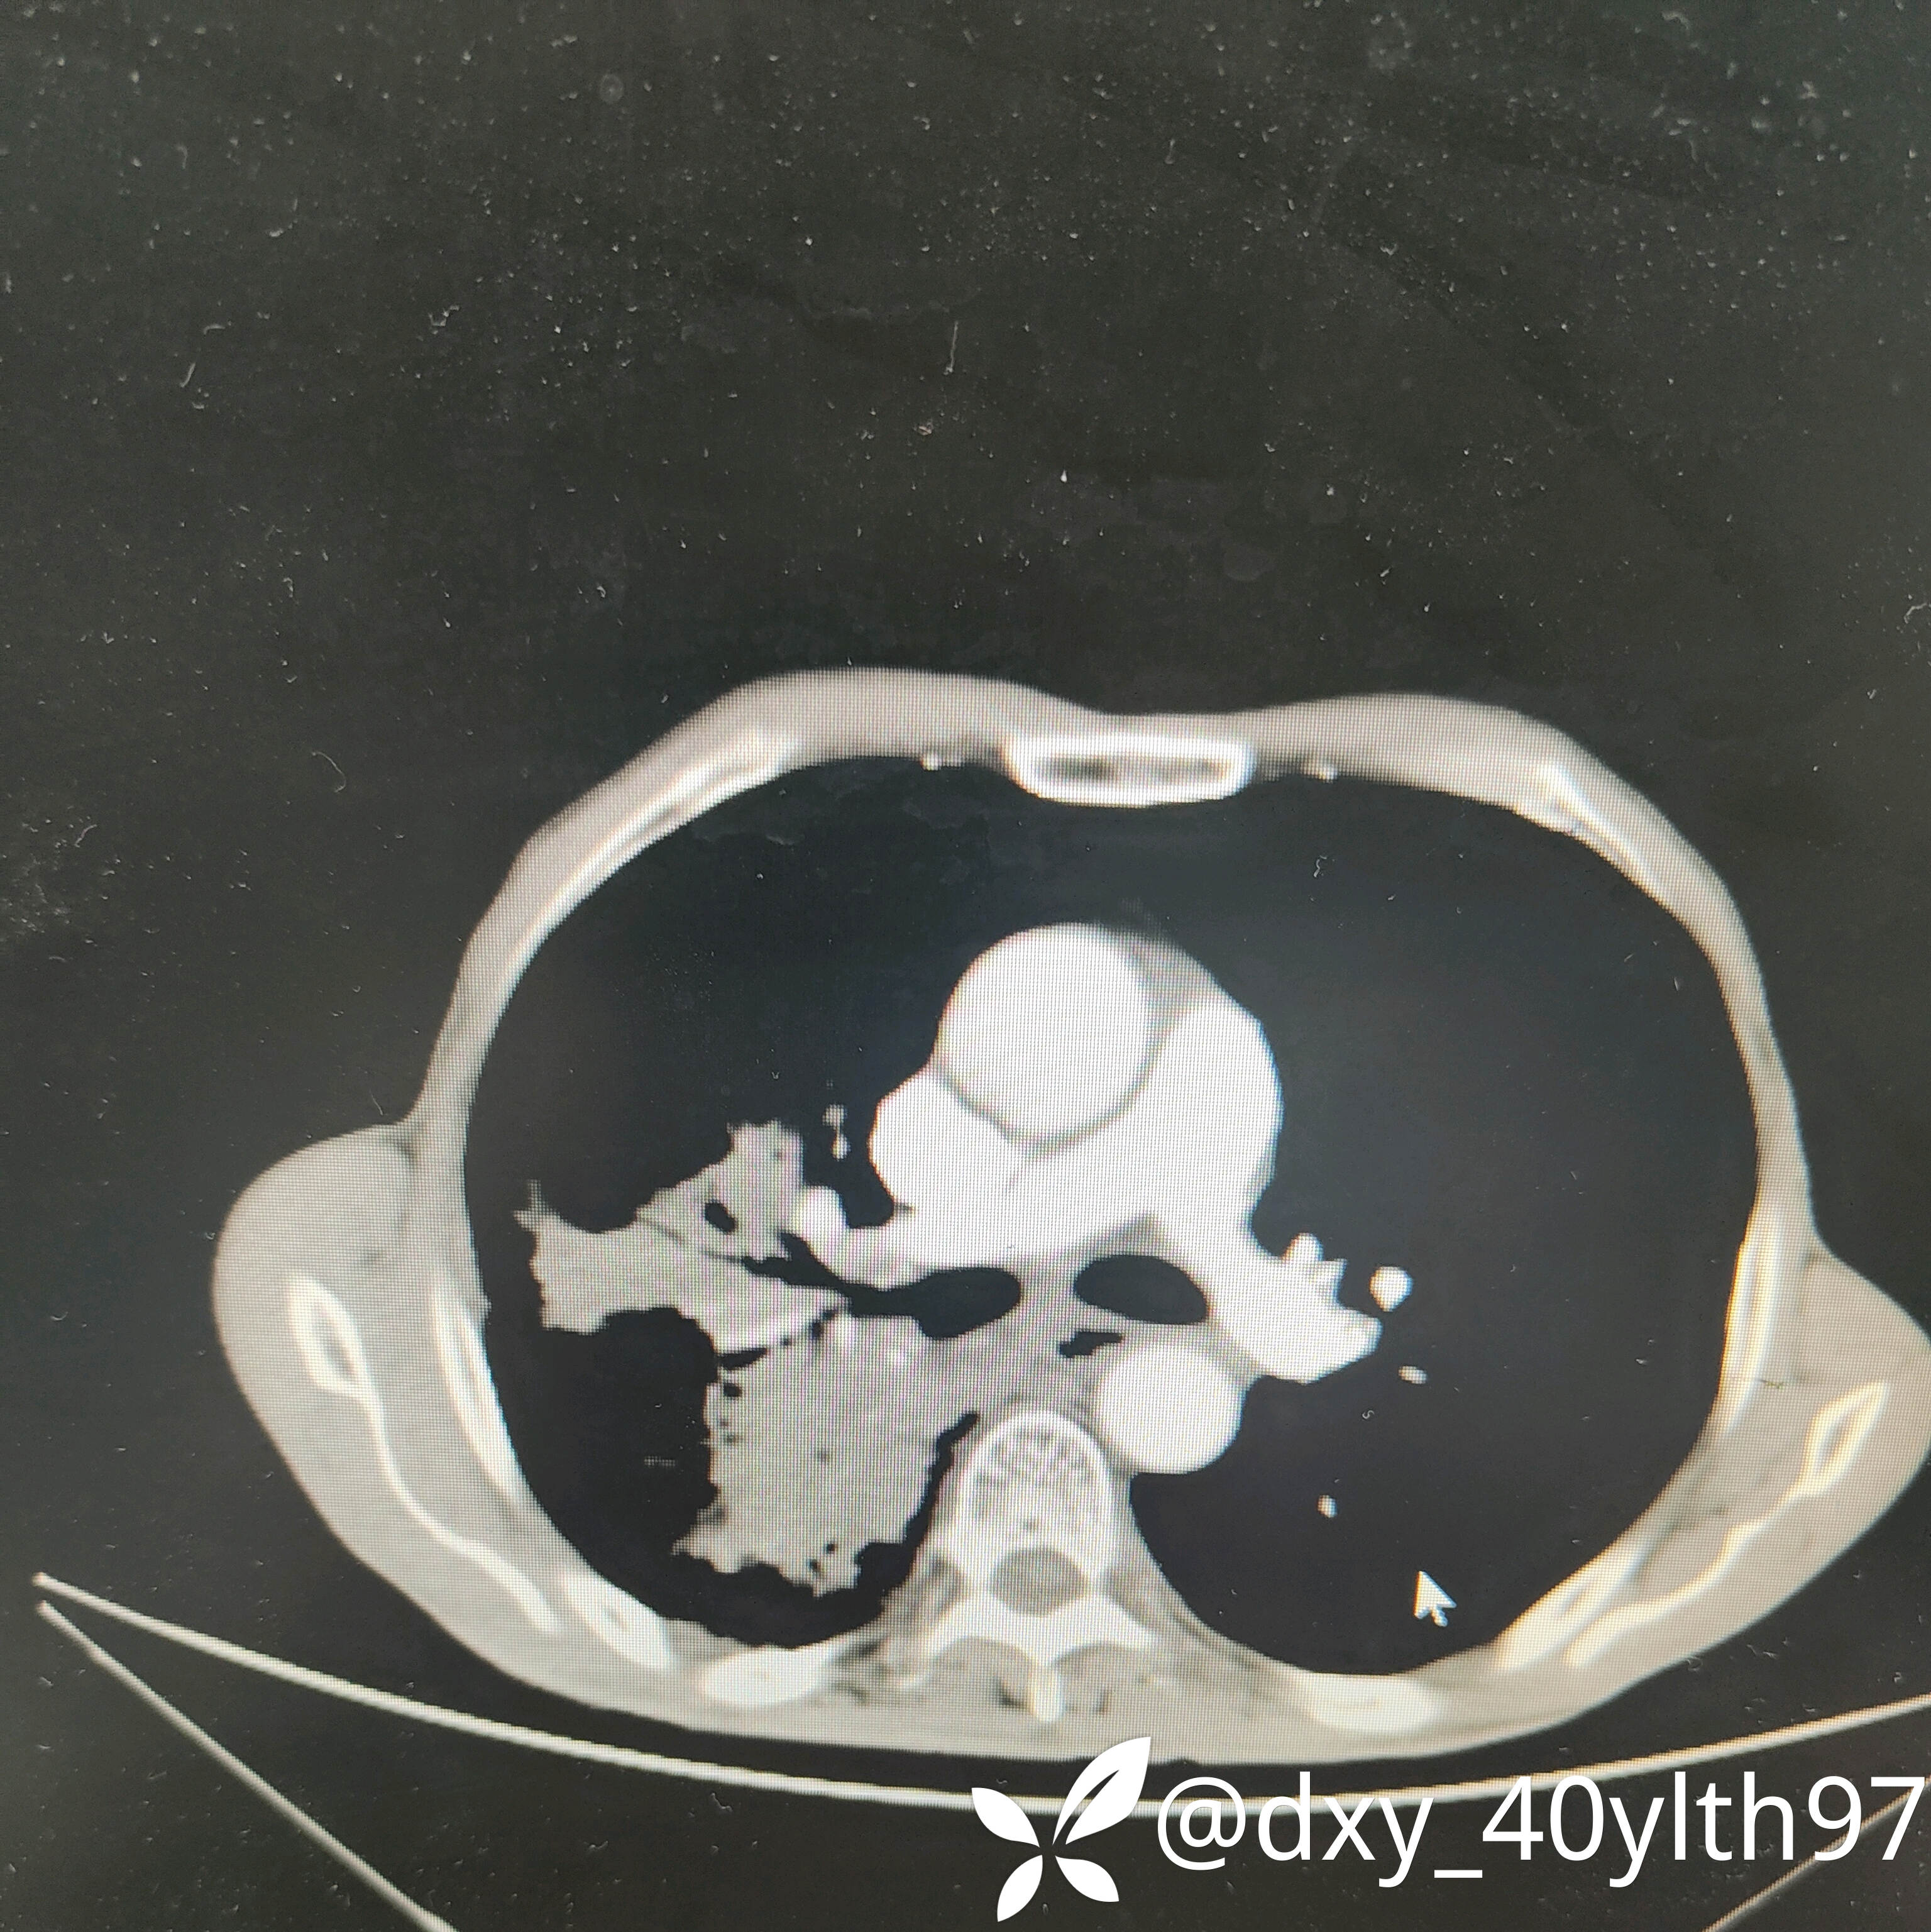

肺部CT平扫+增强提示肿瘤?

治疗经过:2023-8月入院后查肺部CT平扫

2023年8月肺部CT平扫影像结果提示:1.右肺上叶密度增高影较前显著增大,建议进一步检查;2.两肺多发斑片结节灶较前增多,部分增大。

肺部增强CT影像学提示:右肺内大片不规则影轻度强化,肿瘤可能。